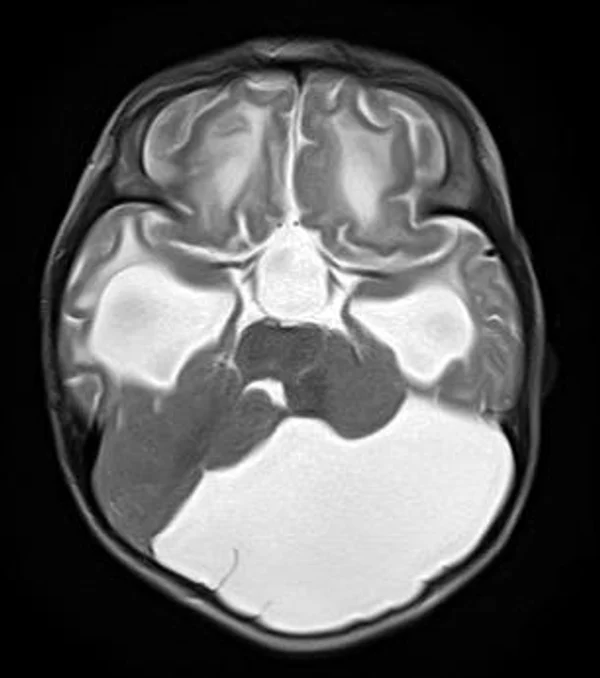

кисты, аномалии Денди-Уокера и др.Операции при внутричерепных кистах. В основном встречаются арахноидальные кисты различных локализаций и кисты сосудистых сплетений боковых желудочков. Пациентам с врождёнными кистами операции проводятся в следующих ситуациях: увеличении объема кисты в динамике, наличии клинических проявлений, компрессии и дислокации мозговых структур, наличии окклюзии ликворных путей. Нами используются 2 способа хирургического лечения кист: эндоскопическая перфорация стенок кист и открытая резекция кист. Открытая резекция кист проводится при ретроцеребеллярных арахноидальных кистах (рис. 2), при арахноидальных кистах межполушарной щели при отсутствии непосредственного контакта их стенок со стенками расширенных желудочков головного мозга и повторного увеличения кист средней черепной ямки после эндоскопической кисто-цистерностомии. Техника операции заключается в проведение краниотомии и максимальном иссечении стенок кист с созданием широкого сообщения кист с субарахноидальным пространством. Эндоскопические операции проводятся при арахноидальных кистах межножковой и пинеальной цистерн, арахноидальных кистах межполушарной щели при тесном контакте их стенок со стенками расширенной желудочковой системы (рис. 3), первично при арахноидальных кистах средней черепной ямки, а также при кистах сосудистых сплетений боковых желудочков. При арахноидальных кистах межножковой цистерны эндоскопически проводится перфорация стенок кисты, сообщая ее с просветом III желудочка и межножковой цистерной – эндоскопическая вентрикуло-кисто-цистерностомия (рис. 4). При арахноидальных кистах пинеальной цистерны проводится перфорация кисты в передне-верхних её отделах с созданием сообщения полости кисты с просветом III желудочка – эндоскопическая кисто-вентрикулостомия. С целью предотвращения облитерации сформированного отверстия иногда в полость кисты под контролем эндоскопа вводится стент перфорированный на протяжении (рис. 5, 6). Эндоскопическая кисто-цистерностомия выполняется при арахноидальных кистах средней черепной ямки. При этом создается широкое сообщение кисты с базальными цистернами. При кистах сосудистых сплетений боковых желудочков проводится их вскрытие в просвет боковых желудочков – эндоскопическая кисто-вентрикулостомия. При множественных кистах проводится их хирургическое сообщение между собой – интеркистосмия